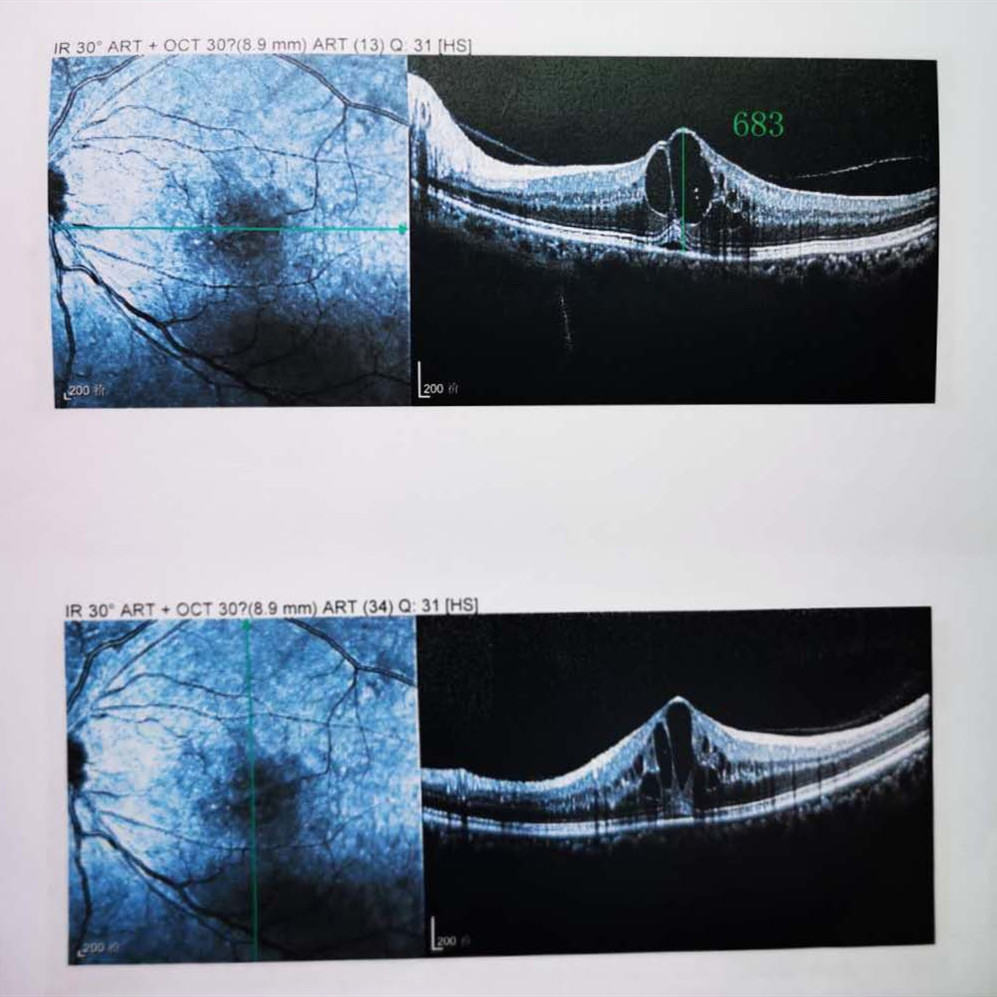

檢查結果顯示,武先生并沒(méi)有近視,右眼視力為1.0,但是左眼視力只有0.4,而且左眼視網(wǎng)膜各分支靜脈迂曲擴張,全網(wǎng)膜面見(jiàn)火焰狀出血,黃斑區高度水腫、滲出,黃斑中心凹厚度約683um。

(武先生初次就診眼底OCT檢查圖)

而正常的矯正視力是1.0,黃斑中心凹厚度在200um左右。

“你這黃斑都腫到正常人的三四倍大了!”廈門(mén)眼科中心吳國基院長(cháng)醫生告訴武先生,“你這是左眼視網(wǎng)膜中央靜脈阻塞伴黃斑水腫,你左眼的視力下降、看東西變形,是因為你左眼視網(wǎng)膜的中央靜脈發(fā)生了阻塞、出血,導致眼底黃斑水腫了。”

那么,武先生的視力恢復情況如何呢?幸運的是,經(jīng)過(guò)兩次玻璃體腔注藥術(shù),武先生左眼的黃斑水腫得到明顯改善,視力已經(jīng)恢復到0.8。

(武先生出院時(shí)眼底OCT檢查圖)